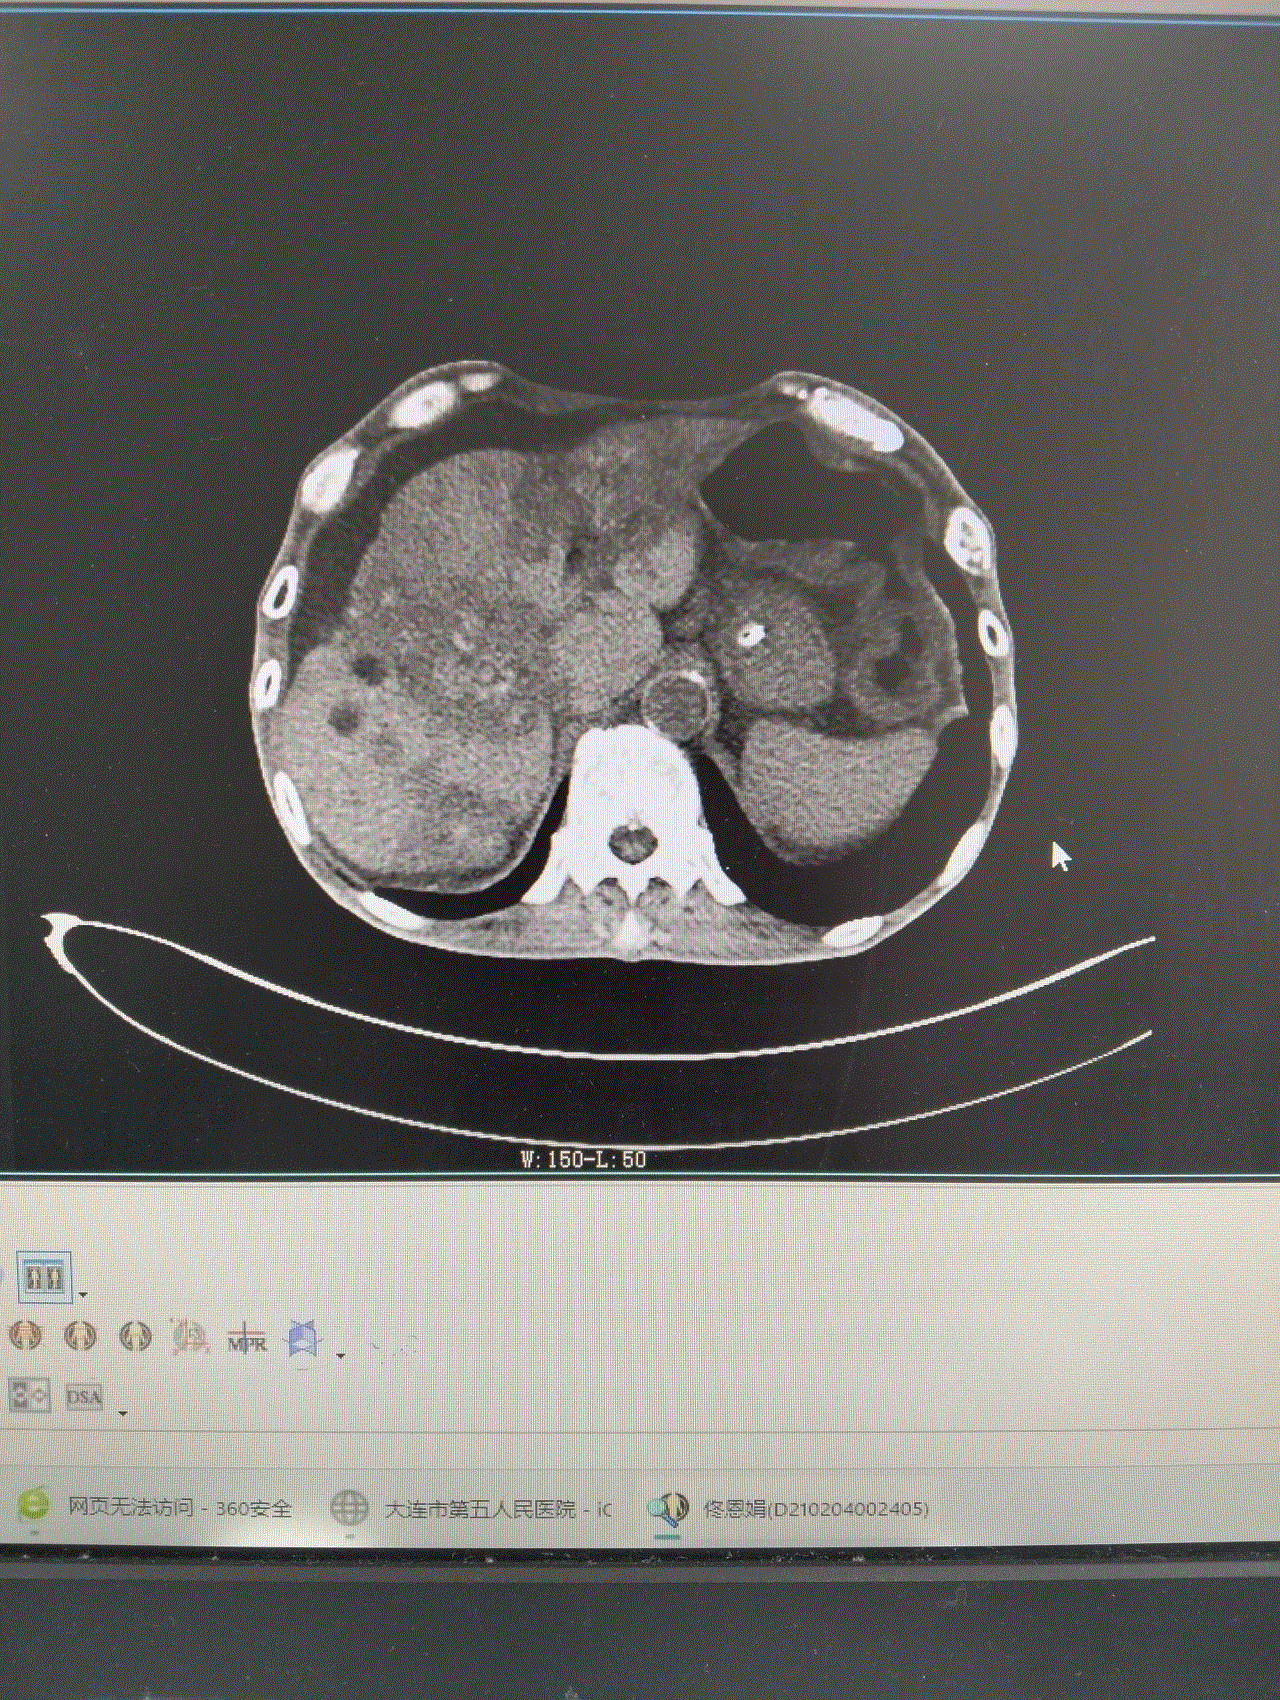

此时的龚大爷,腹部高高隆起,犹如临产的孕妇,叩诊鼓音明显,情况危急!CT显示,龚大爷的结肠严重扩张,脏器被挤压移位。若不及时解除梗阻,随时可能引发腹膜炎、感染性休克,甚至危及生命。然而,常规胃肠减压对低位肠梗阻效果有限,治疗陷入僵局。